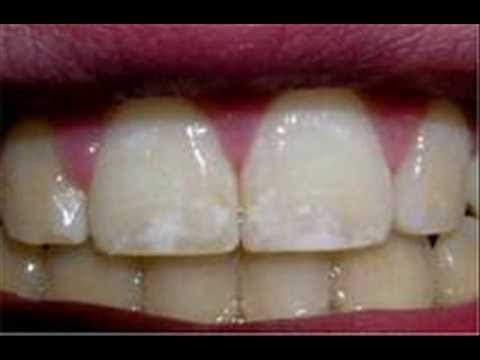

Иллюстрации флюороза молочных зубов